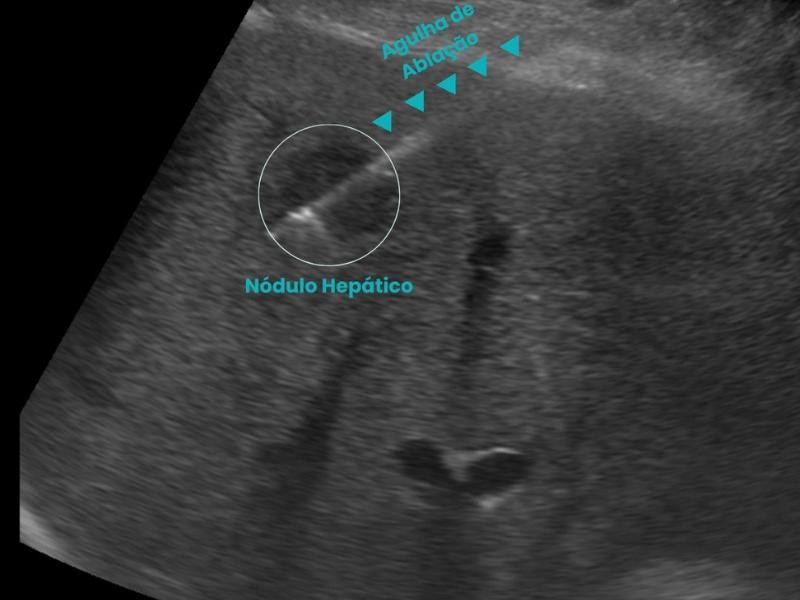

A Biópsia Guiada por Imagem é um procedimento minimamente invasivo que utiliza tecnologias como ultrassom, tomografia computadorizada ou ressonância magnética para orientar a introdução de uma agulha de biópsia até o local exato da lesão. Essa precisão é o que permite a coleta segura de amostras para análise laboratorial. A Biópsia Guiada por Imagem é realizada com equipamentos de última geração, garantindo conforto e segurança do paciente. Além disso, a técnica reduz a necessidade de cirurgias abertas e acelera o diagnóstico, sendo essencial para identificar tumores, infecções e doenças inflamatórias.

Existem diferentes tipos de Biópsia Guiada por Imagem, e cada uma é indicada conforme o tipo e localização da lesão:

A Biópsia Guiada por Imagem é essencial para diagnosticar cânceres de mama, fígado, pulmão, rim, tireoide, além de lesões musculoesqueléticas e linfonodais.

Realizamos procedimentos como ablação de tumores, biópsias guiadas, embolizações e drenagens, com foco na recuperação rápida e no bem-estar dos pacientes. Nosso atendimento é humanizado e nossa equipe é altamente qualificada, sempre em busca de soluções personalizadas.